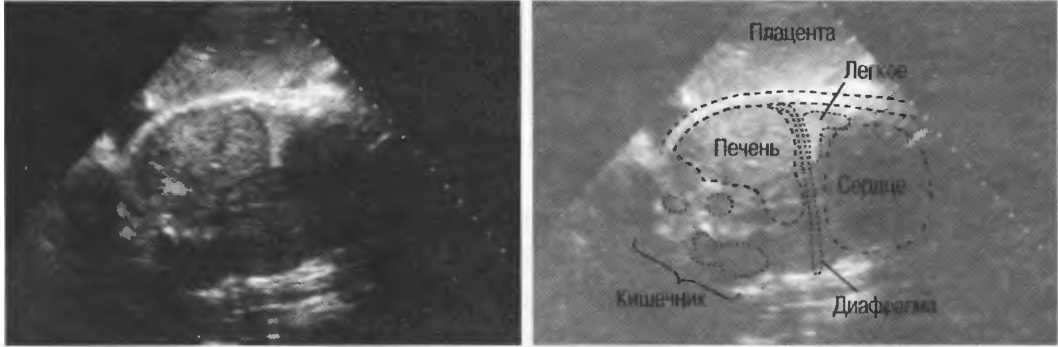

Рис.5. Два поперечных среза плода, демонстрирующих тень от позвоночника плода. Аналогичная тень от ребер может частично закрывать почки или печень. Изменяя угол наклона датчика, можно изменить положение тени таким образом, чтобы подлежащие ткани были видны отчетливо.

Череп плода, дифрагма, стенки сосудов, соединительная ткань являются примерами зеркальных отражателей (рис. 6).